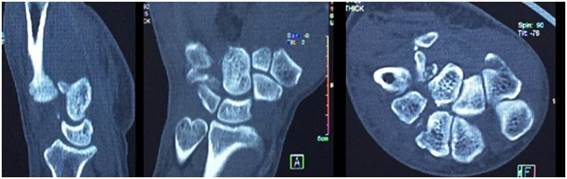

Se presenta el caso de un hombre de 63 años, diestro, artesano en hierro y madera, que sufre accidente de tránsito de alta energía en moto versus auto, sufriendo traumatismo en mano derecha, sin presentar otros traumatismos. Queda de inmediato con dolor y deformidad a dicho nivel por lo que consulta. De la exploración física en el departamento de emergencia se observó la mano derecha con gran deformidad en dorso, bien perfundida, sin lesiones de piel, con movilidad y sensibilidad de los dedos conservada. Se practicaron radiografías con enfoque anteroposterior, oblicua y perfil de la mano que evidencian: luxación dorsal carpo-metacarpiano de los 5 metacarpianos (Figura 1).

Se realizó una tomografía computada de la región que mostró la luxación antes descripta con fractura del sector distal del trapecio, trapezoide, hueso grande y ganchoso (Figura 2).